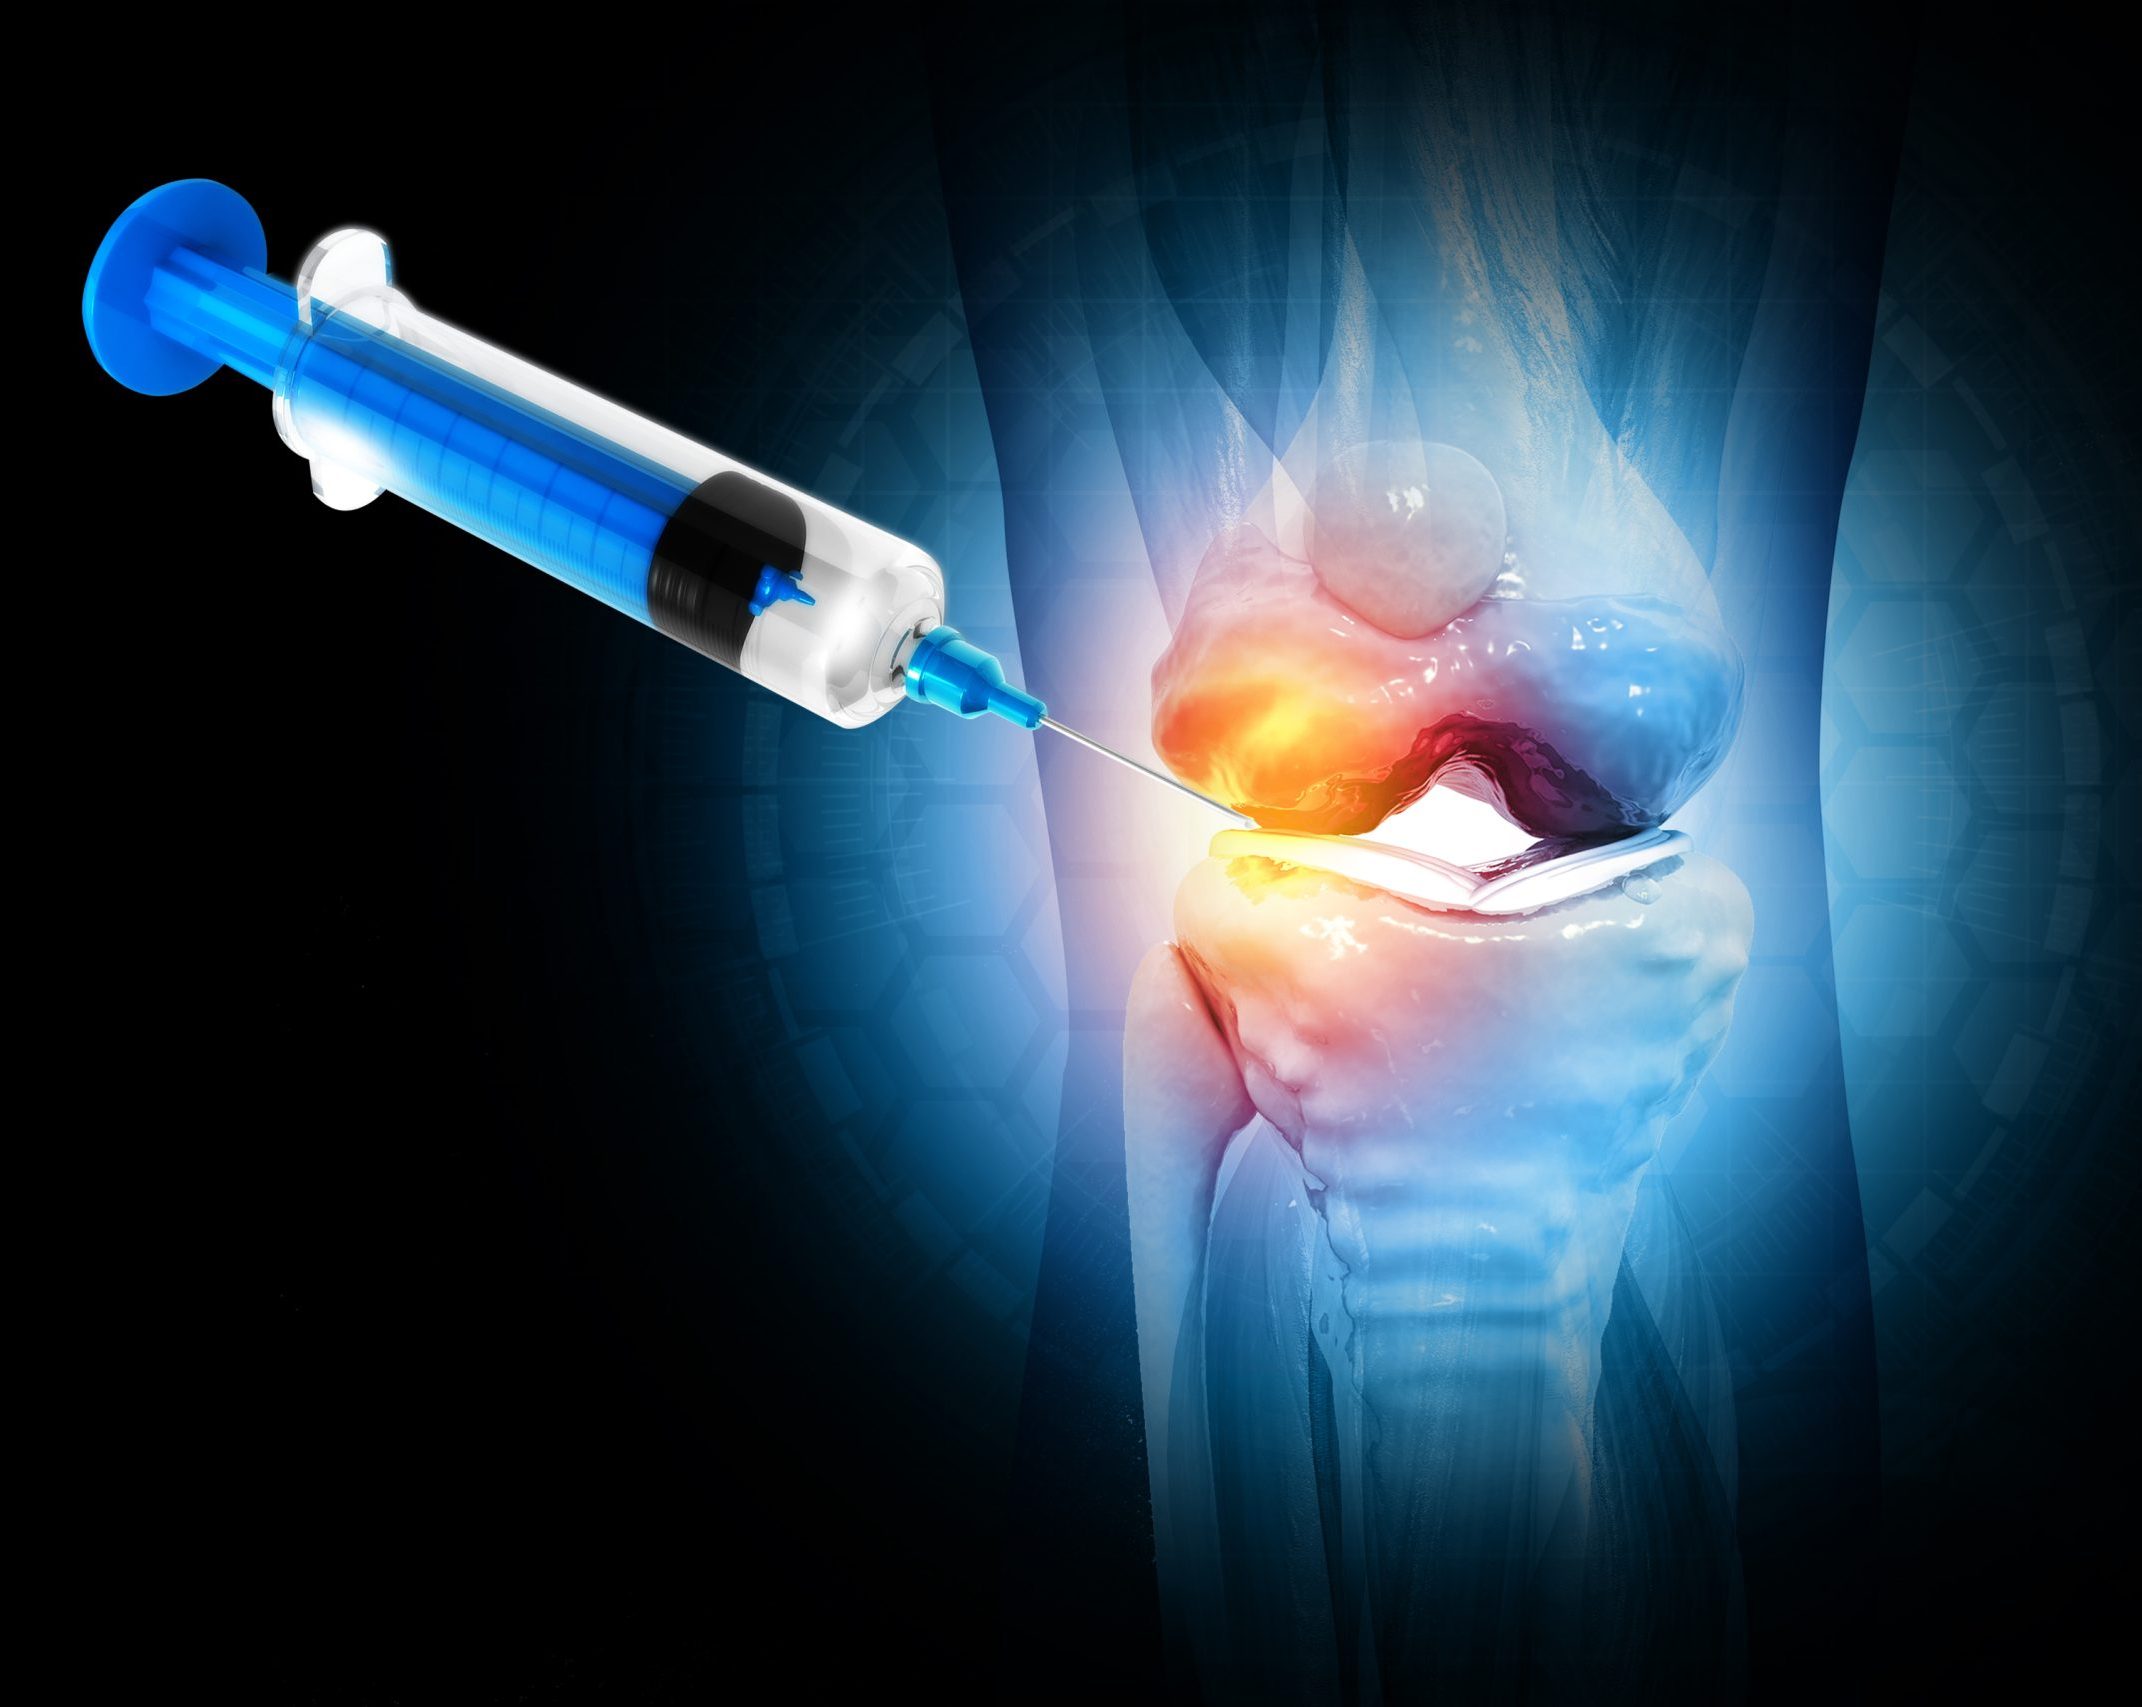

Euflexxa injections deliver a gel-like substance called hyaluronic acid into the joint. This helps lubricate and cushion arthritic joints, reducing pain and improving movement. CT guidance ensures the injection is placed precisely where it’s needed.

At Link Radiology, we use CT imaging to guide the needle accurately into the joint space. This improves treatment effectiveness and reduces risk.